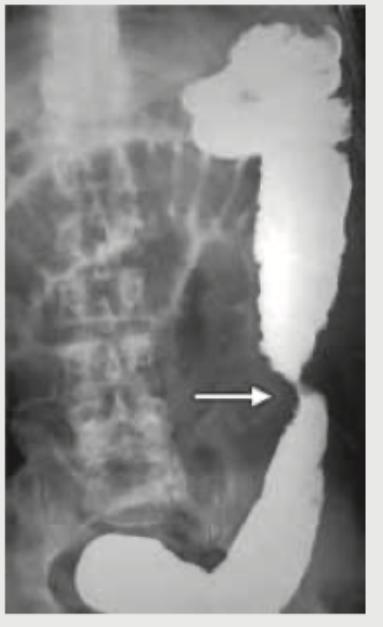

A 62-year-old male presented with signs and symptoms of intestinal obstruction. Radiological image of the patient is given. What is the sign that is illustrated in the image?

Explanation: ***Apple core sign*** - This sign, also known as the **"napkin ring" sign**, is characteristic of a **constricting colorectal carcinoma** seen on barium enema. - The lesion causes a sharp, irregular narrowing of the bowel lumen with overhanging edges, resembling an apple core after a bite has been taken. *Lead pipe sign* - The **"lead pipe" sign** refers to the loss of **haustral markings** and colonic shortening, giving the colon a smooth, rigid, and narrow appearance. - This finding is typically associated with **chronic ulcerative colitis**. *Saw tooth sign* - The **"saw tooth" sign** is characteristic of **diverticulosis**, where the muscular layers of the colon hypertrophy, creating a serrated appearance in the barium column. - This is due to the presence of sacculations and spiky muscular contractions. *Cobble stone* - The **"cobblestone" appearance** describes the irregular, nodular pattern of the mucosal surface of the colon due to **deep ulcerations** crisscrossing with **edematous mucosa**. - This finding is typically seen in **Crohn's disease**, particularly in the small bowel and colon.

Explanation: ***Rectus sheath hematoma*** - The abdominal X-ray (left image) shows a **large soft tissue mass** in the upper abdomen causing displacement of bowel loops. The CT scan (right image) demonstrates a **well-defined, high-attenuation lesion within the rectus sheath**, indicated by the arrow, consistent with a hematoma. - The appearance of a **fluid collection with high attenuation** on CT in the rectus sheath area, along with the mass effect seen on the plain film, is characteristic of a rectus sheath hematoma. *Small intestinal obstruction* - Small bowel obstruction typically presents with **dilated small bowel loops** and **air-fluid levels** on plain radiographs, which are not the primary finding here. - While there is some bowel gas displacement, the prominent finding is a soft tissue mass rather than classic obstructive patterns. *Large intestinal obstruction* - Large bowel obstruction involves **dilated large bowel loops**, often with **haustral folds**, and may present with a collapsed small bowel distal to the obstruction point. - The images do not show a pattern typical of dilated colon or specific features of large bowel obstruction. *Pneumoperitoneum* - Pneumoperitoneum refers to **free air in the peritoneal cavity**, often visible as air under the diaphragm on an upright chest X-ray or as free air outlining abdominal structures on supine films. - The provided images do not show evidence of free intraperitoneal air; instead, they demonstrate a contained soft tissue mass.